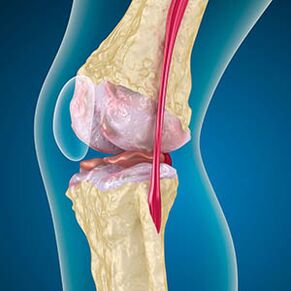

Izmantojot artrozi, skrimšļa oderes kaulu malas nav nobrāzušas vai pilnībā nav. Bojāti audi nav sāpju avots, jo tam nav receptoru. Iekaisums tuvējās struktūrās izraisa raksturīgus simptomus.

Ķermenis turpina bojātu audu atjaunošanos, bet skrimšļi aug nevienmērīgi. Tā rezultātā veidojas pārkāpumi, kas ievaino citus locītavas elementus. Osteofītu raksturs ir izskaidrojams ar kompensāciju par vienmērīgu locītavu skrimšļiem. Cita versija norāda, ka "Spurs" izaugsme Tas ir saistīts ar mēģinājumu stabilizēt locītavu mediāli vai sāniski muskuļu vājināšanas dēļ.